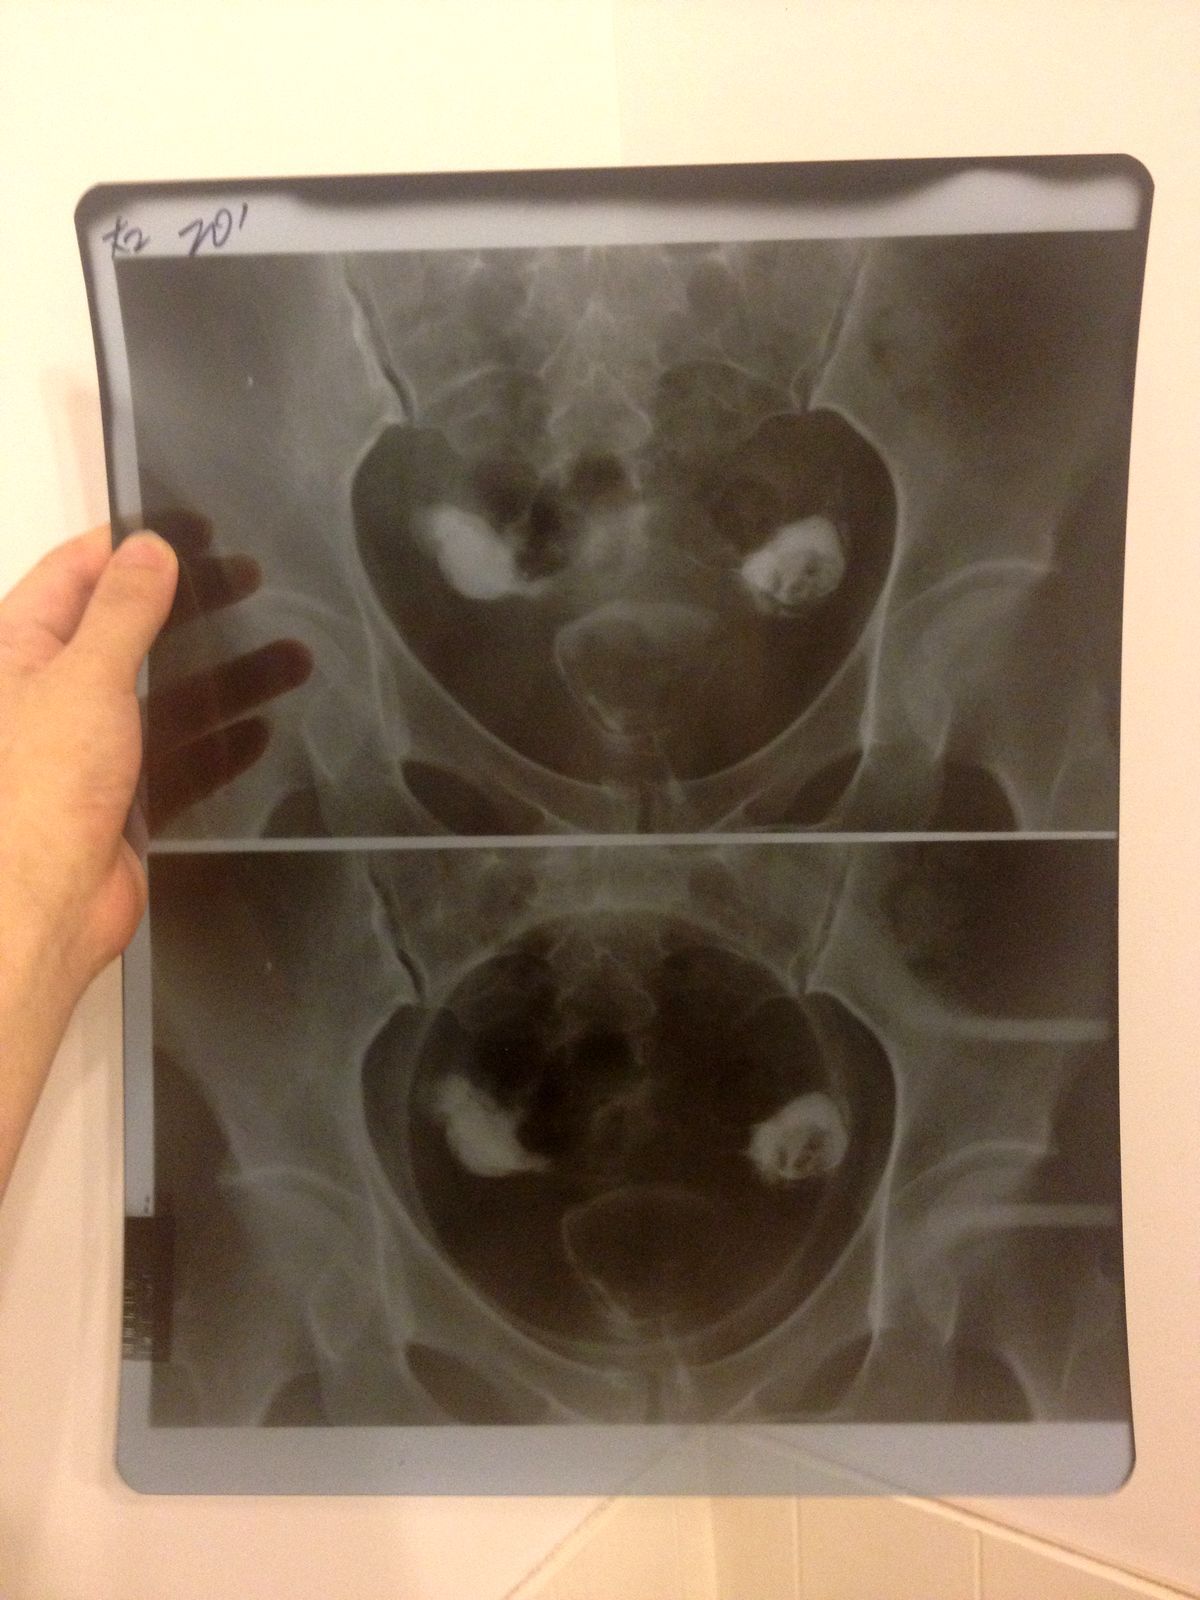

输卵管伞端粘连远端堵塞如何治疗 做造影的医生说你要快就直接宫腔镜,中药吃几年未必有效,毕竟30多了,然后带着片子回医院看,医生说你直接试管吧,堵成这样没用了。换了家民营医院,医生说你没有严重到只能做试管的地步,试管成功率低,等待时间长。然后她给我看了很多病人在试管无效的情况下在她那里做了腹腔镜然后怀孕的病例。身边有个朋友之前也是输卵管堵塞做了腹腔镜,短期没有效果就直接试管了,可是试管失败了,但是没过多久居然怀孕了,可能还是腹腔镜的关系?不知道到底该怎么办,请医生帮我看看我这个到底应该做什么? 点击展开 匿名用户 2014-08-06 12:27 为您推荐: 其他回答 你好,这个时候是要自己注意去医院里检查一下的呢,这个情况是要让医生给好好的处理一下的啊 生活还在继续66 2014-08-07 16:02 相关问题 输卵管伞端未显影是不是就是堵塞或者粘连了? 右侧输卵管远端积水怎,左侧伞端粘连 请问该怎么治疗 急急急 双侧输卵管伞端粘连,远端增粗,用药治疗怀孕的几率有吗??

做造影的医生说你要快就直接宫腔镜,中药吃几年未必有效,毕竟30多了,然后带着片子回医院看,医生说你直接试管吧,堵成这样没用了。换了家民营医院,医生说你没有严重到只能做试管的地步,试管成功率低,等待时间长。然后她给我看了很多病人在试管无效的情况下在她那里做了腹腔镜然后怀孕的病例。身边有个朋友之前也是输卵管堵塞做了腹腔镜,短期没有效果就直接试管了,可是试管失败了,但是没过多久居然怀孕了,可能还是腹腔镜的关系?不知道到底该怎么办,请医生帮我看看我这个到底应该做什么?